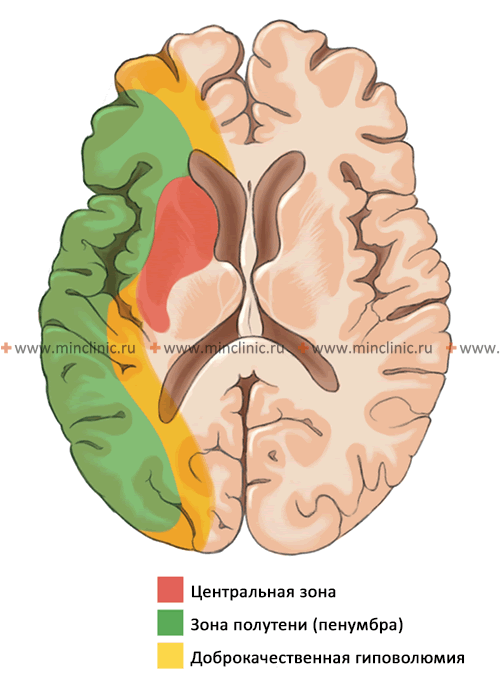

Величина, расположение и в некоторой степени сама природа эмбола определяют размеры, локализацию и характер вызываемого им инфаркта в паренхиме мозговой ткани. Достаточно крупные эмболы, способные закупорить ствол средней мозговой артерии (2-3 мм). Такой вид эмболии приводят к массивным поражениям головного мозга с вовлечением в патологический процесс мозговой коры и подлежащего белого вещества, а также глубокого серого и белого вещества. Небольшой очаг ишемического инсульта формируется в тех случаях, когда эмбол настолько мал, что закупоривает (окклюзирует) мелкую прободающую ветвь, идущую от ствола средней мозговой артерии или от основной артерии.

Следует отметить, что эмбол, представляющий собой тромбоцитарно-фибриновый сгусток, может мигрировать по сосудистому руслу, подвергаться растворению (тромболизис) и расщеплению. Этим обусловливается волнообразный характер симптоматики и в некоторых случаях — полное восстановление вызванного ишемией неврологического дефицита. Локализация и размеры инфаркта головного мозга зависят также от уровня коллатерального кровоснабжения через не подвергшиеся эмболии артерии.

При достаточном обходном (коллатеральном) кровотоке через сосуды виллизиева круга или позвоночную артерию, эмболический фрагмент, перекрывающий вышележащий участок внутренней сонной артерии, нижележащий (А1) сегмент передней мозговой артерии или вышележащий участок позвоночной артерии, может не привести к ишемии или инфаркту головного мозга. Аналогично этому эмболы могут блокировать поверхностную корковую ветвь средней мозговой артерии и даже ствол средней мозговой артерии и приводить не более чем к инфаркту в виде «пятна» в области коры и прилежащего белого вещества полушария головного мозга, если реализуется обходной (коллатеральный) кровоток в корковых зонах смежного кровоснабжения через сращения из передней или задней мозговой артерии к бассейну средней мозговой артерии. Значение этих факторов сохраняется и при инфаркте мозжечка.